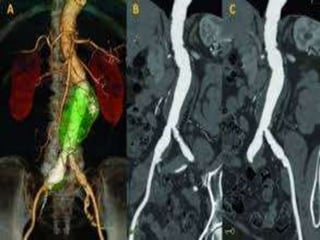

Via renal: administrados de forma intravenosa nos estudos

vasculares (angiografias) tanto de artérias (arteriografia) como de

veias(flebografia) e sistema urinário(urografia intravenosa ou

excretora, cistografia e uretrografia)(*);

Uso de contraste: Uso de contraste:

Flebografia do membro Urografia intravenosa

inferior

Contraste Artificial PositivoIodado Características Se caracteriza por ser hidrossolúvel e facilmente reabsorvido pelo sistema biológico, sendo eliminados por via renal ou via biliar; Via renal: administrados de forma intravenosa nos estudos vasculares (angiografias) tanto de artérias (arteriografia) como de veias(flebografia) e sistema urinário(urografia intravenosa ou excretora, cistografia e uretrografia)(*); Via biliar: estudo da vesícula e vias biliares, sendo administrados por via oral(colecistografia oral) ou por via intravenosa (colangiografia intravenosa); A concentração de iodo no composto influencia na maior ou menor radiopacidade, concentração à 35%, significa 35g de iodo por cada 100ml de diluente. Pode apresentar-se como substância iônica e não iônica.